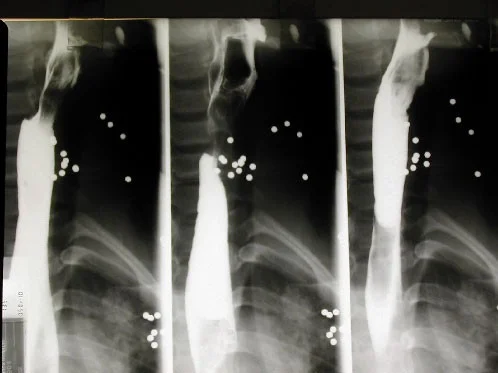

Shotgun pellets 1

Shotgun pellets 2